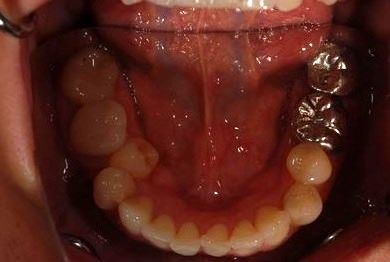

| 性別/年齢 | 女性 / 38歳 | ||||||||||||||||||||||||||||||||

| 主訴 | 右奥歯2本、インレーの相談をしたい。 | ||||||||||||||||||||||||||||||||

| 治療方針 | セラミック治療にて、審美的回復を行う。 | ||||||||||||||||||||||||||||||||

| 治療内容 | ハイブリッドセラミックインレー2本、メタルボンドセラミッククラウン2本(メタルボンド用土台2本)、オールセラミッククラウン1本(オールセラミック用土台1本) | ||||||||||||||||||||||||||||||||